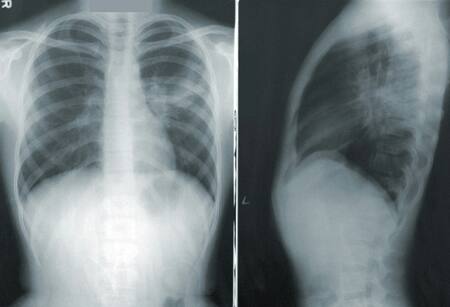

Un nuevo producto mostró resultados asombrosos contra el cáncer de pulmón. Foto: Unsplash

El medicamente, que ya está aprobado y disponible bajo la marca Lobrena en Estados Unidos, fue probado en un ensayo clínico con personas que padecen una forma avanzada de linfoma quinasa anaplásico (ALK) en células no pequeñas de cáncer de pulmón (NSCLC).

La mitad de la muestra recibió lorlatinib. Al resto, por su parte, le administraron crizotinib, un fármaco de generación anterior.